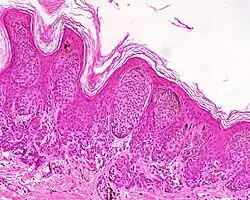

| Intradermal nevus | Within the dermis. | A classic mole or birthmark. It typically appears as an elevated, dome-shaped bump on the surface of the skin.[3][4] |

-

Small dermal nevus, with nests of nevus cells (arrows)

Small dermal nevus, with nests of nevus cells (arrows)